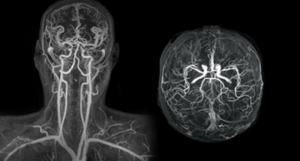

ΔΙΑΓΝΩΣΤΙΚΕΣ ΕΞΕΤΑΣΕΙΣ Καρωτίδων Αρτηριών

Οι διαγνωστικές εξετάσεις των καρωτίδων αρτηριών είναι σημαντικές για την αξιολόγηση της κατάστασης αυτών των αρτηριών που βρίσκονται στον λαιμό και εφοδιάζουν τον εγκέφαλο με αίμα. Οι συνήθεις διαγνωστικές εξετάσεις περιλαμβάνουν:

Οι διαγνωστικές εξετάσεις των καρωτίδων αρτηριών είναι σημαντικές για την αξιολόγηση της κατάστασης αυτών των αρτηριών που βρίσκονται στον λαιμό και εφοδιάζουν τον εγκέφαλο με αίμα. Οι συνήθεις διαγνωστικές εξετάσεις περιλαμβάνουν:

Δοπλερογραφία των Καρωτίδων (Carotid Doppler Ultrasound): Αυτή η εξέταση χρησιμοποιεί υπερήχους για τον εντοπισμό της ροής του αίματος στις καρωτίδες αρτηρίες και για την αξιολόγηση τυχόν αθηροσκλήρωσης ή στενώσεων. Το έγχρωμο Doppler επιτρέπει την οπτικοποίηση της κατεύθυνσης και της ταχύτητας της ροής του αίματος.

Αγγειογραφία των Καρωτίδων (Carotid Angiography): Η αγγειογραφία χρησιμοποιείται για τον εντοπισμό και την αξιολόγηση τυχόν αρτηριακών στενώσεων ή ανευρύσματος στις καρωτίδες αρτηρίες. Συνήθως, ενέχει τη χρήση ενός χρωματιστικού υγρού που επιτρέπει την ορατότητα των αγγείων στις ακτινογραφίες.

Μαγνητική Αξονική Τομογραφία (Magnetic Resonance Angiography - MRA): Η MRA χρησιμοποιείται για τη δημιουργία εικόνων των αγγείων χωρίς τη χρήση ακτινοβολίας. Είναι χρήσιμη για τον εντοπισμό στενώσεων, αθηροσκλήρωσης ή ανευρυσμάτων.

Εξέταση του Σφυγμού των Καρωτίδων (Carotid Pulse Examination): Ο ιατρός μπορεί να ελέγξει τον σφυγμό στις καρωτίδες για να αξιολογήσει τη ροή του αίματος.

Οι παραπάνω τεχνικές συνήθως χρησιμοποιούνται για την αξιολόγηση της υγείας των καρωτίδων αρτηριών και την πρόληψη του εγκεφαλικού επεισοδίου.

Μαγνητική Αγγειογραφία (MRA)

Η Μαγνητική Αγγειογραφία (MRA) είναι μια μη επεμβατική εξέταση που χρησιμοποιεί τη μαγνητική τεχνολογία και τους υπολογιστές για να δημιουργήσει λεπτομερείς εικόνες των αγγείων στο εσωτερικό του σώματος, συμπεριλαμβανομένων των αρτηριών και των φλεβών. Η MRA χρησιμοποιεί το μαγνητικό πεδίο και ραδιοκύματα για τη δημιουργία λεπτομερών εικόνων των αγγείων, χωρίς τη χρήση ακτινοβολίας.

Η Μαγνητική Αγγειογραφία (MRA) είναι μια μη επεμβατική εξέταση που χρησιμοποιεί τη μαγνητική τεχνολογία και τους υπολογιστές για να δημιουργήσει λεπτομερείς εικόνες των αγγείων στο εσωτερικό του σώματος, συμπεριλαμβανομένων των αρτηριών και των φλεβών. Η MRA χρησιμοποιεί το μαγνητικό πεδίο και ραδιοκύματα για τη δημιουργία λεπτομερών εικόνων των αγγείων, χωρίς τη χρήση ακτινοβολίας.

Υπάρχουν διάφοροι τύποι MRA, και ορισμένοι από τους συνηθέστερα χρησιμοποιούμενους περιλαμβάνουν:

Time-of-Flight MRA (TOF-MRA): Αυτή η μέθοδος εκμεταλλεύεται τη διαφορά στη ροή του αίματος για να δημιουργήσει εικόνες των αγγείων. Είναι ευαίσθητη στη ροή του αίματος και συνήθως χρησιμοποιείται για την αξιολόγηση των αρτηριών.

Contrast-Enhanced MRA (CE-MRA): Σε αυτήν τη μέθοδο, ενέσεις με χρωστικές ουσίες που είναι ορατές στις εικόνες μαγνητικής αγγειογραφίας εισέρχονται στην κυκλοφορία του αίματος για να προσδώσουν αντίθεση στις εικόνες. Αυτή η μέθοδος παρέχει πιο λεπτομερείς εικόνες των αγγείων και είναι ευαίσθητη στη ροή του αίματος.

Η MRA χρησιμοποιείται συχνά για την αξιολόγηση των αγγείων σε διάφορα μέρη του σώματος, συμπεριλαμβανομένων των καρωτίδων, της κοιλιακής αορτής, των εγκεφαλικών αγγείων και άλλων περιοχών. Είναι χρήσιμη για την ανίχνευση στενώσεων, ανευρυσμάτων, ή άλλων ανωμαλιών στο σύστημα κυκλοφορίας του αίματος.